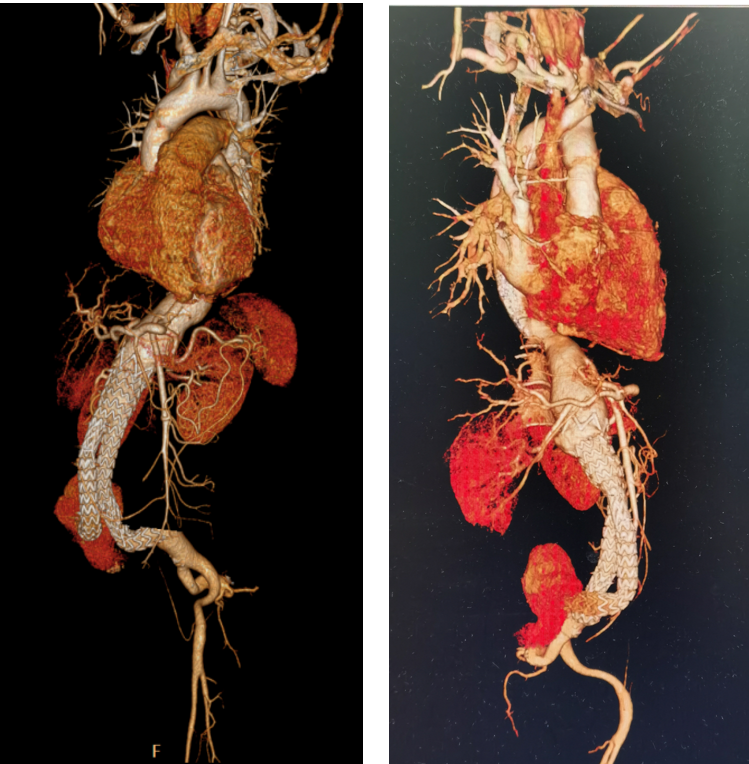

CTA显示:腹主动脉及双侧髂总动脉瘤样扩张,最大横截面积约12.5×8.9cm;支架外动脉瘤呈混杂密度,增强后右侧髂总动脉见不规则造影剂进入动脉瘤内(提示Ⅰb型内漏)。

治疗决策:患者年轻,已出现先兆破裂征象,且支架近远端均存在内漏,主动脉仍在继续扩张。单纯腔内再干预难以解决整个病变主动脉的脆弱性,因此我们选择胸腹联合切口行胸腹主动脉瘤切除+人工血管置换+腹主动脉瘤内覆膜支架异物取出术。术中见支架已脱入瘤腔,主动脉壁薄弱。

术后10天CTA显示人工血管通畅。

病例小结:MFS患者EVAR术后,即使初期成功,远期仍可能因主动脉进行性扩张而发生内漏、瘤体增大甚至破裂。开放手术切除病变血管并取出支架,是年轻患者的根治性选择。